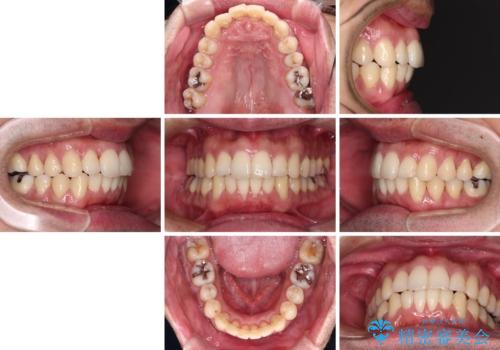

下顎骨が顕著に右側にずれている インビザラインによる咬合改善

- 3年8ヶ月

最終的にはゴムかけなどを活用して改善することができましたが、4年近い治療期間を要することとなりました。